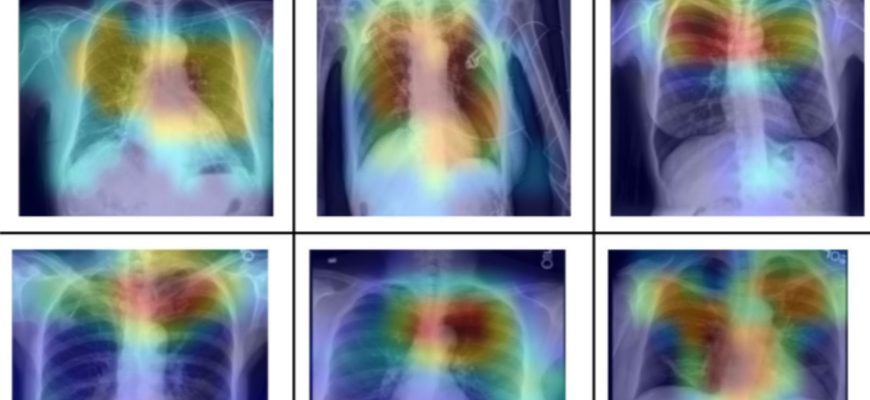

ИИ в пульмонологии: Как мы автоматизировали анализ рентгеновских снимков легких Привет, друзья! Сегодня мы хотим поделиться с вами невероятно захватывающим

ИИ для анализа изображений грудной клетки: Как мы автоматизировали рутину и что из этого вышло В медицине, как и во многих других областях, рутина порой